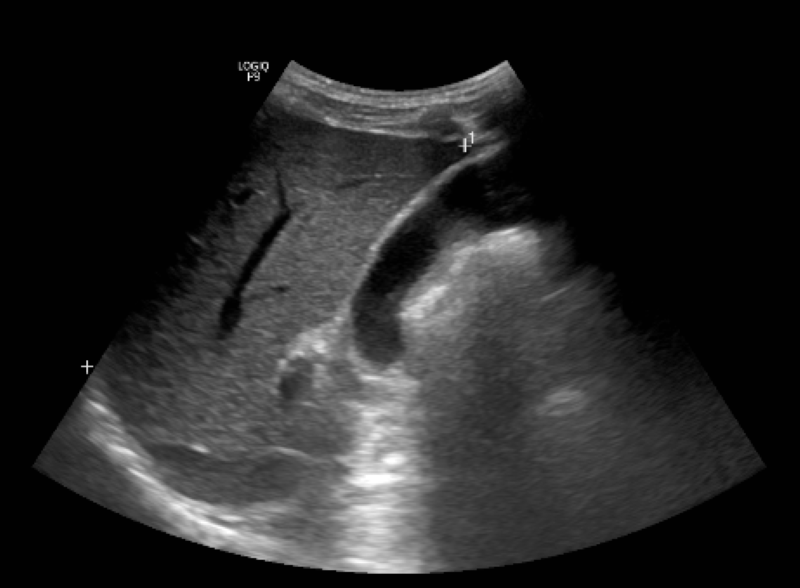

Hình ảnh siêu âm đàn hồi mô gan cho thấy nhu mô gan thô, độ cứng của gan tương đương F4 (theo phân loại Metavir -LB). Bác sĩ chẩn đoán xác định, bệnh nhân mắc tình trạng xơ gan do viêm gan B, được kê thuốc điều trị và hẹn lịch tái khám.

Hình ảnh siêu âm đàn hồi mô gan của bệnh nhân. Ảnh: BVCC